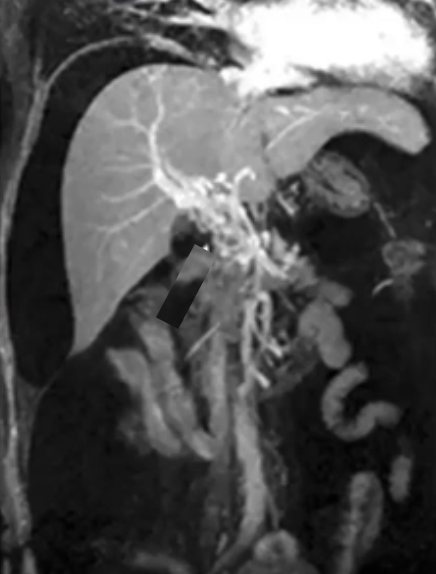

慢性门静脉血栓形成和经颈静脉肝内门体分流术

这些患者大多表现出门静脉高压的症状,而非缺血症状。通常还会伴有出血现象,这使得溶栓药物的使用变得困难。

此外,患者肝脏通常较小且为肝硬化状态,可能还存在海绵状转化,因此经皮穿刺并非可行的选择。

在这种情况下,“Salem ”技术是最佳选择,即进行脾脏穿刺,疏通血栓,放置圈套器,并引导经颈静脉肝内门体分流术(TIPS)操作。